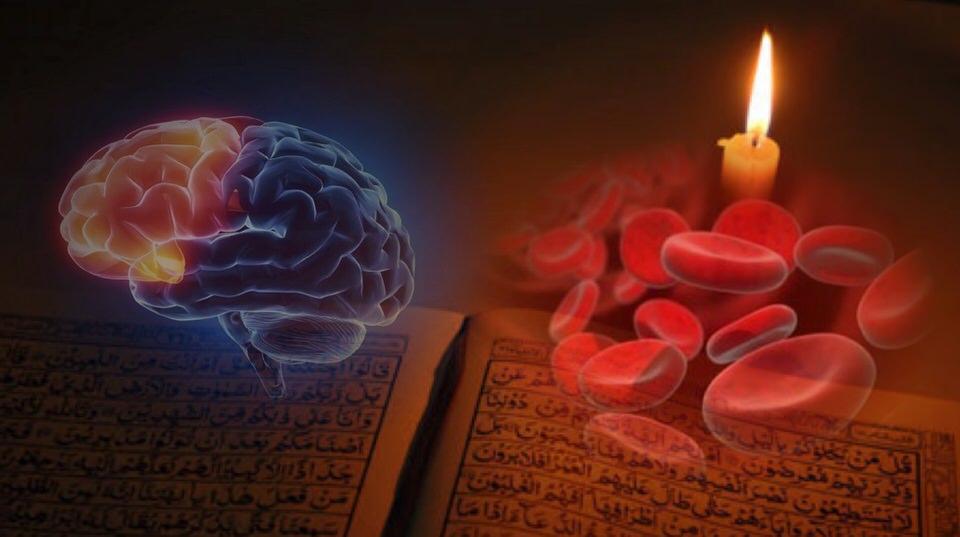

AlQuran telah menyentuh perihal Anatomi dan Fisiologi jauh sebelum masyarakat saintis meneroka kehebatan tubuh manusia. Sebagai contoh catatan pada sistem peredaran darah yang disebut dalam bahasa inggeris sebagai Circulatory System atau Cardiovascular System yang menjurus kepada peranan utama organ jantung pada tubuh manusia.

Firman Allah swt pada surah Qaf ayat 16 yang bermaksud “Dan demi sesungguhnya, Kami telah mencipta manusia dan Kami sedia mengetahui apa yang dibisikkan oleh hatinya, sedang Kami lebih dekat kepadanya daripada urat lehernya.” Jelas ayat ini merujuk kepada salah satu dari urat utama dalam sistem peredaran darah yang disebut “Jugular Vein”.

ALQURAN berbicara anatomi dan fisiologi jauh sebelum masyarakat saintis meneroka kehebatan tubuh manusia. Sebagimana perawatan bekam itu menjurus kepada perkara yang bersangkutan dengan darah, maka kami mulakan dengan catatan AlQuran pada sistem peredaran darah yg disebut dlm bahasa inggeris sebagai Circulatory System. Ianya juga disebut Cardiovascular System yang menjurus kepada peranan utama organ jantung pada sistem peredaran darah.

SISTEM PEREDARAN DARAH

Beberapa aspek sistem kadiovaskular telah disentuh AlQuran dan AlHadith yang membincangkan kepentingan jantung, darah dan peredarannya dan bagaimana penjagaan keduanya amat diperlukan dalam kehidupan.

Hubungan Allah dengan makhluknya jelas digambarkan pada ayat 16 dari surah Qaf.

VENA JUGULAR

وَلَقَدْ خَلَقْنَا الْإِنْسَانَ وَنَعْلَمُ مَا تُوَسْوِسُ بِهِ نَفْسُهُ وَنَحْنُ أَقْرَبُ إِلَيْهِ مِنْ حَبْلِ الْوَرِيدِ

“Dan demi sesungguhnya, Kami telah mencipta manusia dan Kami sedia mengetahui apa yang dibisikkan oleh hatinya, sedang (pengetahuan) Kami lebih dekat kepadanya daripada urat lehernya “

Ayat diatas merujuk secara langsung kepada salah satu urat yang penting dalam sistem peredaran darah iaitu urat leher atau “jugular vein” yang menjadi sebahagian dari rangkaian vena yang berfungsi membawa darah yang mengandungi kabon dioksida kembali kejantung untuk disegarkan semula dengan oksigen dalam proses pernafasan di paru-paru.

Setelah AlQuran menyentuh URAT VENA, Allah SWT melengkapakan sistem peredaran darah dengan menyentuh satu lagi urat utama iaitu ARTERI yang menjadi sebahagian dari rangkaian utama yang disebut AORTA pada ayat 44-46 dari surah yang ke69 AlHaqqah.

Perkataan “Al-Watin” pada ayat ini telah diterjemahkan kepada beberapa makna yang kesemuanya terjurus pada maksud yang sama iaitu “AORTA”, yang merupakan “nadi kehidupan”. Disini kita dimaklumkan oleh Allah SWT akan fungsinya aorta dan rangkaian arteri yang menjana kehidupan manusia kerana sekiranya terputus rangkaian ini maka kematian akan menyusul hampir dengan serta-merta.

Mari kita teliti bentuk organ Jantung pada gambar sisipan. Kita akan dapati ada tiga cabang pada aorta sejurus selepas meninggalkan jantung. Sekiranya kita bayangkan jantung sebagai pusat rezeki dan peredaran darah sebagai sebuah kenderaan, persimpangan pertama yang akan dilalui oleh kenderaan darah ini ialah bahagian kepala dan juga kedua belah “sayap’ tubuh yang merangkumi bahu dan kedua belah tangan yang disebut dalam istilah anatomy sebagai "UPPER EXTREMITIES"